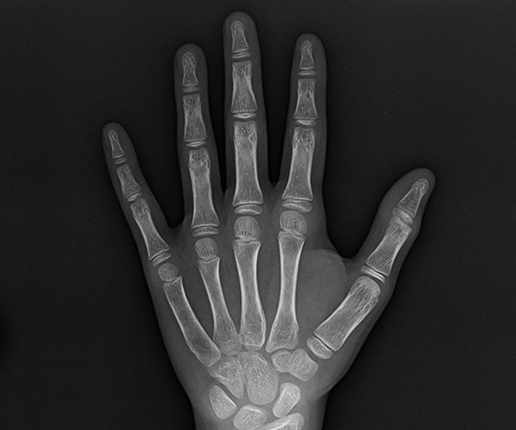

小朋友長高的精華時段為3~16歲間,如果已經超過22歲就幾乎長不高了,所以要從小開始預防。骨齡的判斷包含手骨、腳骨跟髖骨嗎?過敏、金屬中毒、黑眼圈及皮膚癢等症狀,都是影響長高因素!